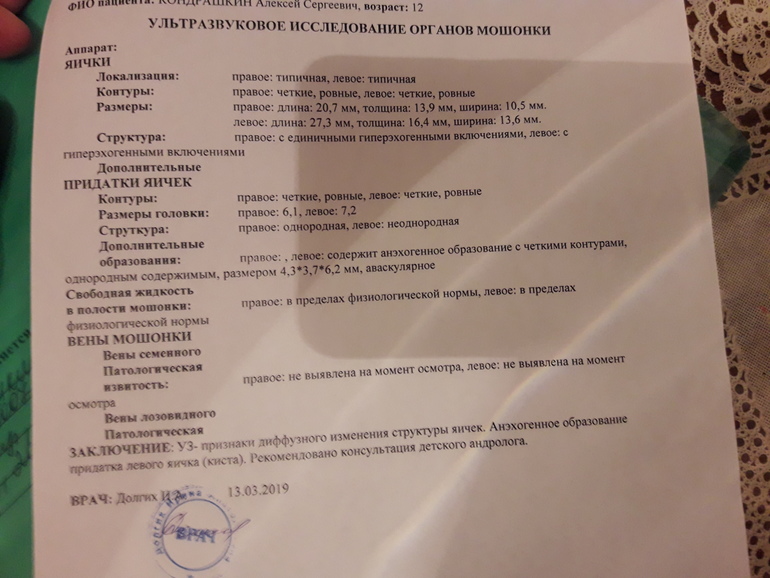

Здравствуйте.сделали узи мошенки мальчику 12 лет.показало диффузные изменения паренхимы яичек.фото прикрепляю(делали 2раза,в разных медцентрах).Подскажите,что это значит.опасаюсь самого страшного.К детскому хирургу попадем только через 3 дня,к андрологу через 4.помогите хоть немного прояснить ситуацию.(изначально обратились к урологу с проблемой задержка мочейспускания-чтобы помочиться ждет некоторое время...)спасибо.